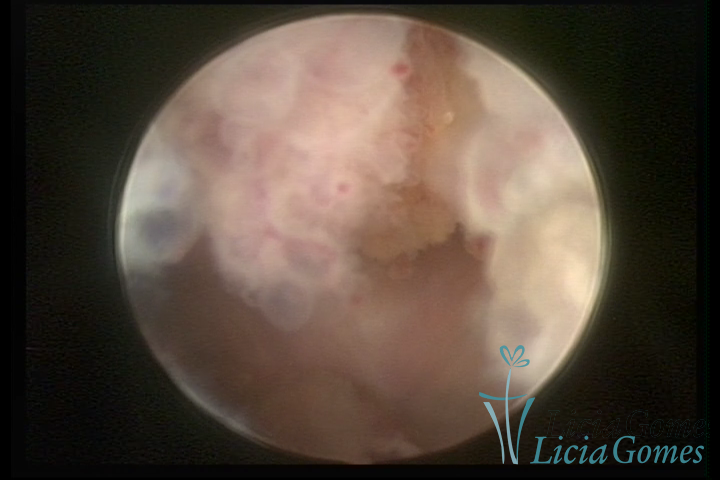

A histeroscopia permite analisar as características da superfície endometrial, não podendo avaliar a profundidade ou o grau de invasão miometrial.

Mas poderá verificar se as lesões são do tipo: focal; regional ou difusa

Este pode apresentar uma gama variável de aspectos macroscópicos, com aspecto pseudopolipoide; lembrando tecido cerebroide ou com reação deciduoide;a vascularização superficial é mais evidente e com vasos em formatos de saca-rolha ou espirais visualizando também a vascularização com atípias, com aumento do calibre dos vasos superficiais, pode ser encontrado também tecido em necrose, poderá haver um pequenos dendritos (papilomatoso).